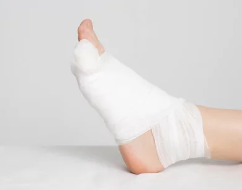

발가락 골절은 심각한 경우 수술이 필요할 수 있지만, 대다수의 경우 비수술적 치료로 관리할 수 있습니다. 골절 치료의 목적은 뼈를 고정하고 자연스럽게 붙을 수 있도록 돕는 것입니다.

비수술적 치료

- 발가락 고정: 주로 부목이나 테이핑을 사용하여 부러진 발가락을 옆의 정상적인 발가락에 고정시켜, 뼈가 올바른 위치에서 자연스럽게 붙도록 도와줍니다.

- 얼음찜질: 골절 직후 얼음찜질을 통해 통증과 부기를 줄일 수 있습니다. 15~20분간 얼음을 올려놓고, 2시간 간격으로 반복하는 것이 좋습니다.

- 압박 붕대: 부드러운 압박 붕대를 사용하여 붓기를 완화하고, 발가락을 안정시키는 데 도움을 줍니다.

- 휴식: 발가락 골절의 회복 과정에서 휴식은 매우 중요합니다. 체중 부하를 최소화하고, 목발을 사용하여 발가락에 압력을 줄이지 않도록 해야 합니다.